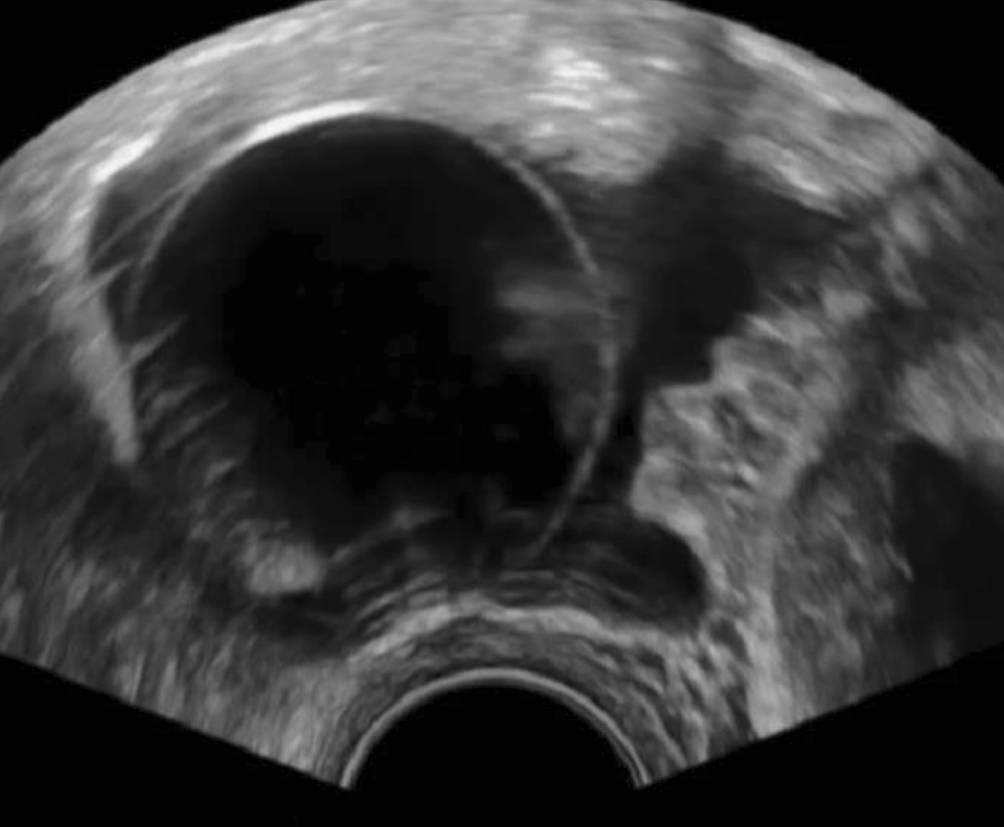

NuvaRing

Zum Abschluss sollte noch der NuvaRing erwähnt werden, der ein charakteristisches sonographisches Erscheinungsbild aufweist – im normalen Schnittbild hat er eine nahezu rechteckige Form, hinter der ein Schatten liegt, wie man ihn von Hormonspiralen kennt (Abb. 7). Es gibt Fallberichte von Anwenderinnen, die den NuvaRing versehentlich in der Harnblase platzierten, dieser kann mit entsprechend gefüllter Blase im Ultraschall gesehen und zystoskopisch entfernt werden [8].

Abb. 7

Ein NuvaRing imponiert als rechteckiger, echoarmer Block unmittelbar hinter der Zervix